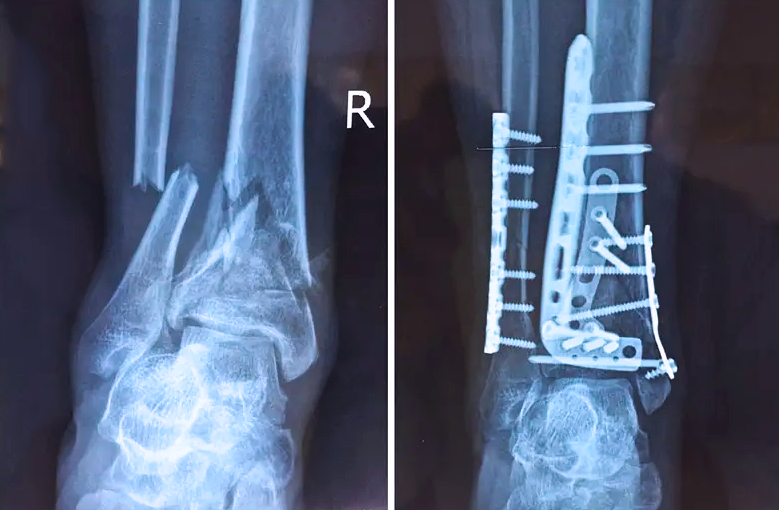

踝關(guān)節(jié)是人體中負(fù)重較大的關(guān)節(jié),也是活動(dòng)度較大的地方,所以對(duì)于足踝部位的關(guān)節(jié)內(nèi)骨折,我們更需要做到“解剖復(fù)位”。對(duì)于這種關(guān)節(jié)內(nèi)的骨折,尤其是踝關(guān)節(jié)內(nèi)部的骨折,不僅需要進(jìn)行X影像平片正側(cè)位的拍攝,由于在二維影像上無(wú)法判斷關(guān)節(jié)面的受損情況,往往還需要進(jìn)行三維影像的檢查。

在術(shù)前,我們需要做三維掃描的CT檢查,我們必須要有CT的片子,還要有三維的重建。

在術(shù)中,我們?cè)趺慈ヅ袛嚓P(guān)節(jié)面平不平整呢?常規(guī)的正側(cè)位影像是不能判斷的。有些醫(yī)生為了準(zhǔn)確的判斷,可能會(huì)選擇做開(kāi)放性的手術(shù),把關(guān)節(jié)暴露出來(lái),在眼睛的直視下判斷關(guān)節(jié)面平不平整。但是關(guān)節(jié)全部打開(kāi),無(wú)疑增加了病人的創(chuàng)傷,而且增加了患者的恢復(fù)時(shí)間。所以如果在術(shù)中我們有三維影像的支持,對(duì)醫(yī)生做手術(shù)而言就會(huì)事半功倍,而且能夠大大的增加手術(shù)準(zhǔn)確度,增加患者術(shù)后的預(yù)后。所以在術(shù)中有三維影像的支持是非常必要的!